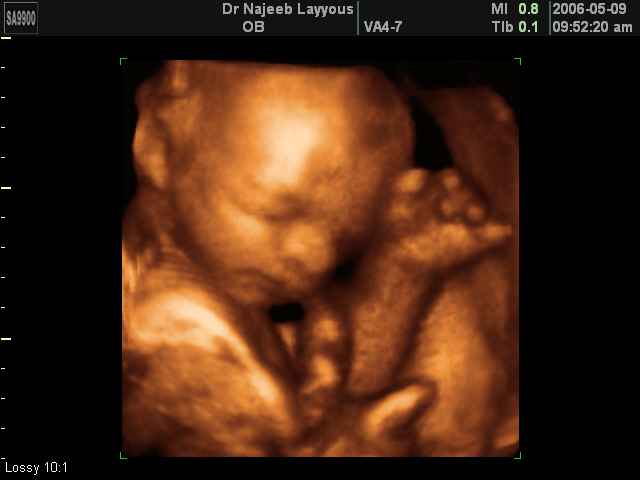

- صور لوجه الجنين في داخل الرحم

- صور لتصرفات الجنين داخل الرحم

صور لتصرفات الجنين داخل الرحم بجهاز الالتراساوند ثلاثي الأبعاد | الدكتور نجيب ليوس